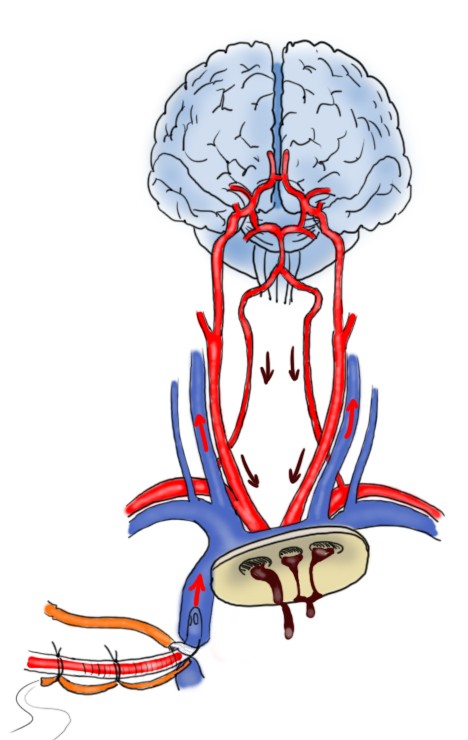

L’immagine sopra mostra un esempio di perfusione cerebrale anterograda selettiva. Raggiunta la temperatura target, il flusso della macchina cuore-polmone è arrestato e l’arco aortico può essere aperto. Sotto visione diretta, il chirurgo inserisce due piccole cannule nel tronco arterioso anonimo e nell’arteria carotide comune di sinistra. Le cannule apporteranno al cervello un flusso di sangue ossigenato (circa 10 ml/Kg/min). In questo modo, mentre il resto del corpo è in arresto il cervello continua ad essere perfuso. Questo tipo di perfusione cerebrale è comune negli interventi in cui la cannula arteriosa che collega la macchina cuore-polmone al paziente è posizionata in arteria femorale. Un piccolo difetto di questa tecnica è il fatto che le cannule per la perfusione invadono il campo operatorio e possono essere di intralcio al chirurgo. Il più recente utilizzo dell’arteria ascellare come sito di cannulazione arteriosa ha aperto la strada a una interessante modifica della metodica di perfusione cerebrale anterograda.